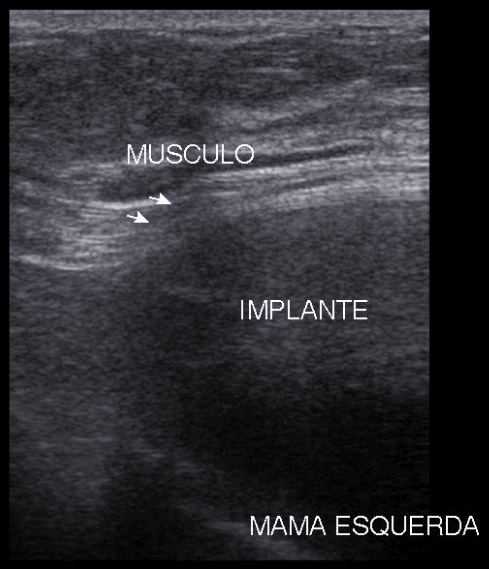

prótese mamária

Ultrassonografia de mamas demonstrando um implante de silicone localizado atrás do músculo peitoral maior (retromuscular).